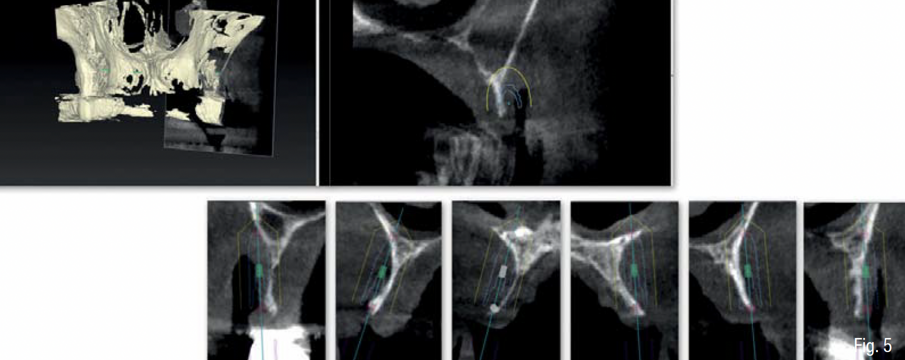

In accordo con il paziente si decide di eseguire un intervento di rigenerazione ossea guidata (GBR) mediante una griglia in titanio customizzata e membrane riassorbibili (Figg. 2-4). Pertanto, 1 mese prima della chirurgia, è stato creato un modello osseo virtuale in formato .stl del mascellare sup. tramite segmentazione, a partire dai file .dicom della CBCT, utilizzando un software biomedicale dedicato (BTK- 3D, Biotec Srl, Dueville, Vicenza, Italy); è stato quindi eseguita la progettazione virtuale dell’aumento di volume osseo necessario per inserire gli impianti e la successiva progettazione della griglia customizzata al di sopra del volume aumentato; infine, è stata realizzata la griglia in titanio vera e propria mediante tecnologia di stampa 3D basata su sinterizzazione laser del titanio (3D-Mesh BTK, Biotec Srl, Dueville, Vicenza, Italy) (Figg. 5-8).

Infine, è stata eseguita un’attenta chiusura di prima intenzione dei lembi chirurgici, mediante una sutura a doppio strato, costituita da una linea di punti a materassaio orizzontale e da una linea di punti staccati singoli, per garantire una chiusura ermetica della ferita (SERAFAST 5/0, Serag-Wiessner, Naila, Germany) (Figg. 18, 19). Nei 7 giorni consecutivi il paziente ha proseguito la terapia antibiotica a base di amoxicillina e acido clavulanico e una terapia antiinfiammatoria a base di nimesulide; risciacqui con clorexidina 0.20% 3 volte al giorno per 2 settimane; e non ha utilizzato la protesi parziale rimovibile sempre per 2 settimane. Dopo 9 mesi, essendo stata confermata una sufficiente mineralizzazione del volume osseo al di sotto della griglia mediante una CBCT post-operatoria (Figg. 20-22), è stata pianificata una chirurgia computer-guidata per inserire gli impianti in modo protesicamente guidato (Figg. 23, 24).